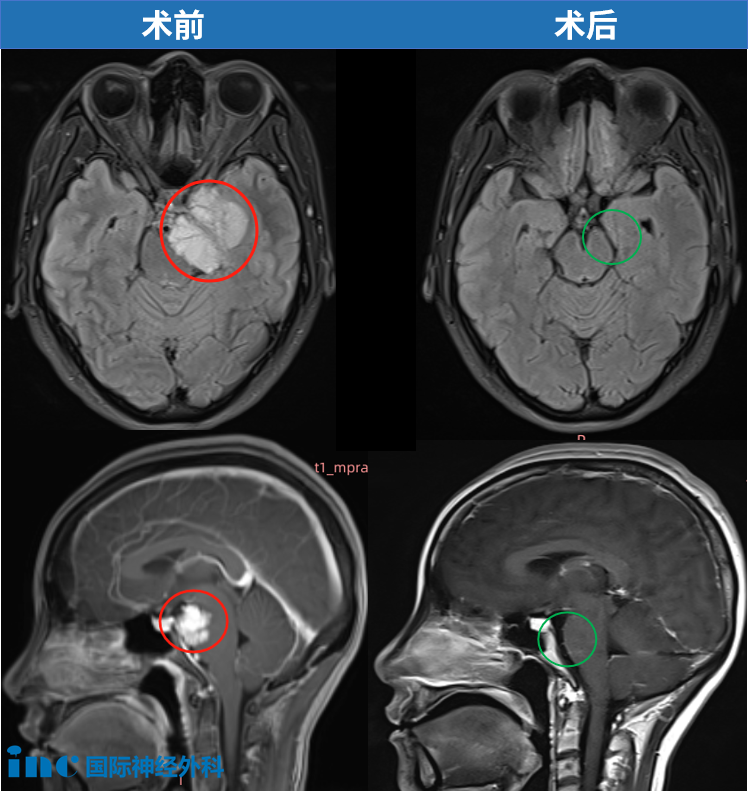

病灶现已完全消失。影像学检查显示无肿瘤残留或复发迹象,所...